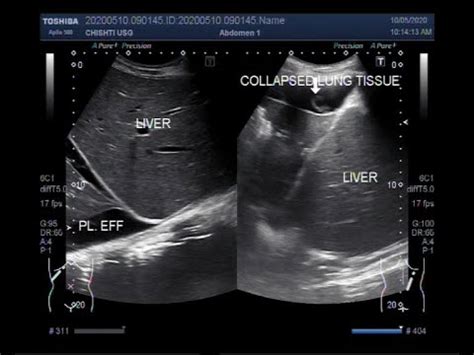

In this case we can see the liver, kidney, the diaphragm, and you can see that triangular wedge shaped area of black which is fluid or pleural effusion and you can actually see what we call the spine sign, which is the proximal thoracic ribs or lateral vertebral processes.

Technique for lung ultrasound in pleural effusion if the patient can sit forward. Rather, any underlying disease that has been identified (congestive heart failure thoracic ultrasound for pleural effusion in the intensive care unit: This video shows bilateral pleural effusion with a septated effusion with adherences between lung base and diaphragm on left side. In this case we can see the liver, kidney, the diaphragm, and you can see that triangular wedge shaped area of black which is fluid or pleural effusion and you can actually see what we call the spine sign, which is the proximal thoracic ribs or lateral vertebral processes. Pleural effusions are generally classified as transudates or exudates, based on the mechanism of fluid formation and pleural fluid chemistry. Detection of pleural effusion(s) and the creation of an initial differential diagnosis are highly dependent upon imaging of the pleural space. Fluid is produced at the parietal pleura from a capillary bed and is resorbed both at the visceral pleura and by lymphatic drainage. I also thought that chf was bilateral pleural effusion but i guess you can have unilateral too.